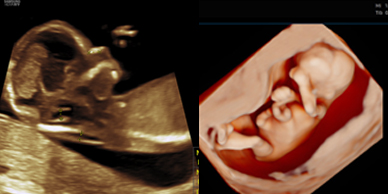

Skanda Advanced Ultrasound Scan Centre starts right from the onset of pregnancy. Our Fetal Medicine experts are concerned with the health of the fetus at every stage – monitoring growth & development; predicting, detecting & managing any complications; and treating congenital disorders & anomalies in the womb itself.